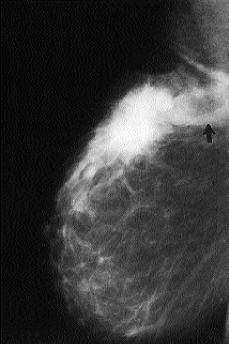

En todos los casos, excepto el número 1, tanto la mamografía (Fig. 3) como la ecografía detectaron la presencia de los ganglios intramamarios. Todos ellos se presentaron como nódulos bien circunscritos. En la ecografía practicada in vitro en el ganglio del caso 4 se apreciaron las características propias de las adenopatías metastásicas como son una morfología esférica y ausencia de la región hiliar (Fig. 4).

Fig. 3. Mamografía donde se observa un tumor y una imagen nodular cercana que corresponde a un ganglio linfático intramamario metastásico (flecha) (caso 4).